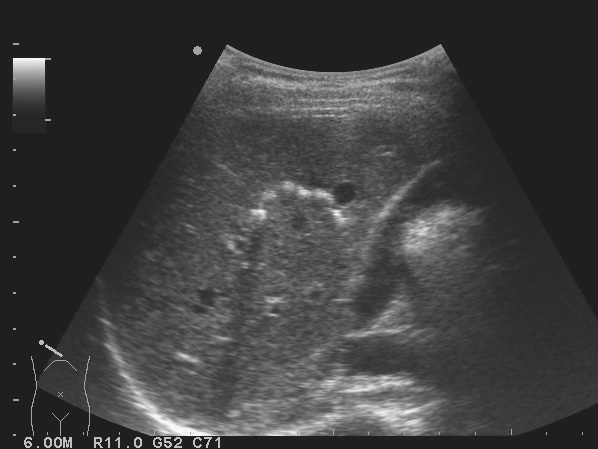

(2)肝内胆管结石

1)肝内出现点状或团状强回声后方伴声影,强回声沿肝内胆管分布(图2-6-6)。

图2-6-6 肝内胆管结石灰阶超声图像

2)结石近端的肝内胆管可有不同程度扩张,扩张的肝内胆管与伴行的门静脉形成平行管征。

3)结石强回声周围可见细窄无回声区环绕。结石处胆管前后壁显示清楚。

4)结石一般不随体位改变而移动。结石可引起胆管梗阻、胆汁淤积或炎症感染,进而出现肝大,肝实质回声增粗,内部回声不均匀,或可见多发肝脓肿、肝实质萎缩变性等表现。